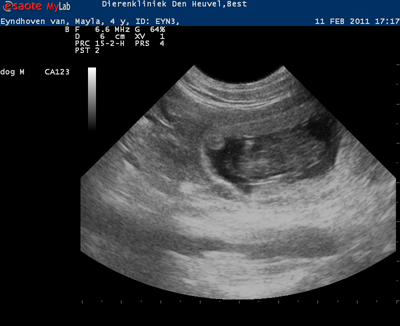

We couldn't wait anymore now so on February 2 we went to the vet for an ultrasound and.. YES!!! She is pregnant!!!

But it's not going to be a big litter. Sad for the people on the waiting list, but we are happy that she is pregnant.

Next week we are going back for a new ultrasound.

The puppies are expected around March 10.